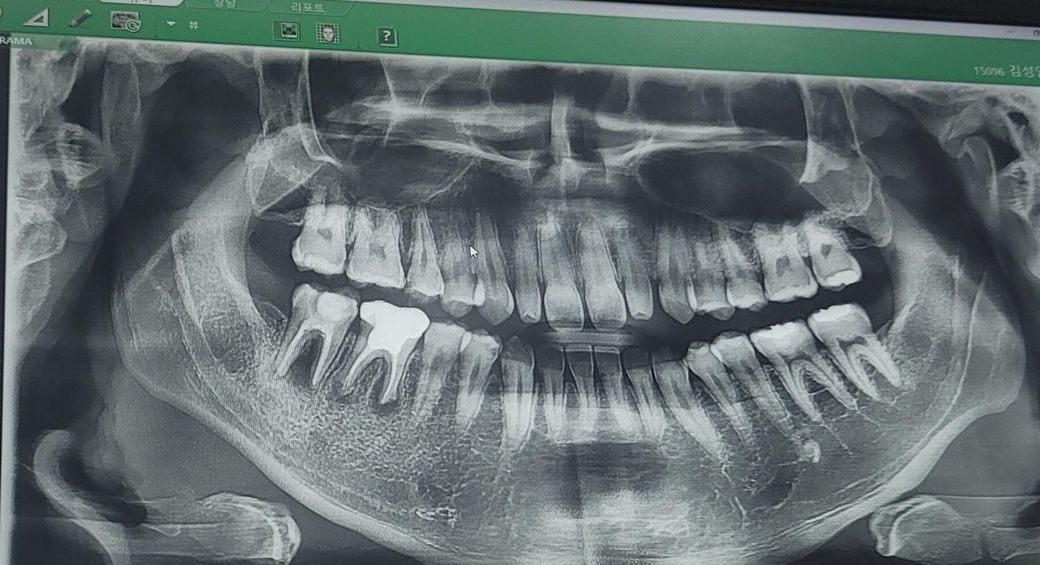

맨뒤 어금니 두개 판단좀 부탁드립니다

우측 어금니 두개 병원두개를가도 못살린다고 임플란트 무조건하라는데

이게맞을까요?? 그리고 충치 6개가나왓는데 엑스레이로 판단가능한가요?

오른쪽 아래 맨 뒤에 있는 치아의 경우에는 치조골 손실이 매우 심하기 때문에 발치가 필요할 것으로 생각됩니다. 그 앞에 있는 치아 또한 치조골 손실이 있지만 뿌리 쪽에만 손실이 있기 때문에 이런 경우 신경 치료 등으로 염증을 제거해 보는 시도를 해 볼 수 있습니다. 하지만 치아를 살릴 확률이 높지는 않습니다.

1. 오른쪽 하방의 어금니 2개는 잇몸뼈가 녹을 정도로 염증이 많이 퍼졌습니다. 발치를 염두해두고 재신경치료를 해볼 순 있으나 성공확률이 높진 않을 것 같습니다.

2. 정확한 충치 검사는 파노라마 사진보다는 치근단 사진으로 하는게 좋습니다만 위 사진상 작은 어금니 옆면으로 충치가 있는게 관찰되긴 합니다.